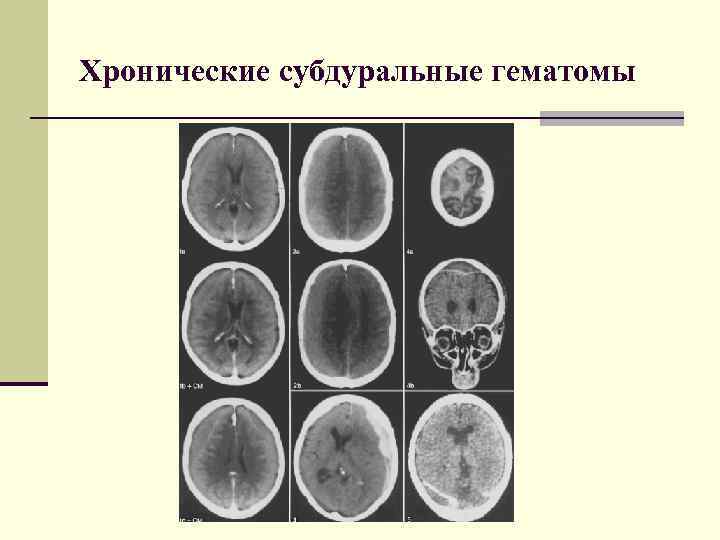

Хронические субдуральные гематомы. Классификация По локализации: I. Односторонние Двухсторонние II. Лобные 1. Лобно-теменные 2. Хронические субдуральные гематомы. Классификация По локализации: I. Односторонние Двухсторонние II. Лобные 1. Лобно-теменные 2. Лобно-височные 3. Лобно-теменно-височные 4. Лобно-теменно-затылочно-височные 5. Теменно-височно-затылочные Височные 1. Теменно-височные 2. Височно-затылочные

Хронические субдуральные гематомы. Классификация 1. 2. 3. 4. По плотности: Гиподенсивные Гиперденсивные Гетероденсивные Изоденсивные Хронические субдуральные гематомы. Классификация 1. 2. 3. 4. По плотности: Гиподенсивные Гиперденсивные Гетероденсивные Изоденсивные

Хронические субдуральные гематомы. Варианты плотности а) гиподенсивная б) гиперденсивная в) изоденсивная г) гетероденсивная Хронические субдуральные гематомы. Варианты плотности а) гиподенсивная б) гиперденсивная в) изоденсивная г) гетероденсивная

Хронические субдуральные гематомы. Классификация 1. 2. 3. 4. 5. По отношению к поверхности мозга: Хронические субдуральные гематомы. Классификация 1. 2. 3. 4. 5. По отношению к поверхности мозга: Сагиттальные Парасагиттально-конвекситальные Конвекситальные Базальные

Хронические субдуральные гематомы. Классификация По строению: 1. 2. 3. Однокамерные Двухкамерные Многокамерные Хронические субдуральные гематомы. Классификация По строению: 1. 2. 3. Однокамерные Двухкамерные Многокамерные

Хронические субдуральные гематомы Хронические субдуральные гематомы